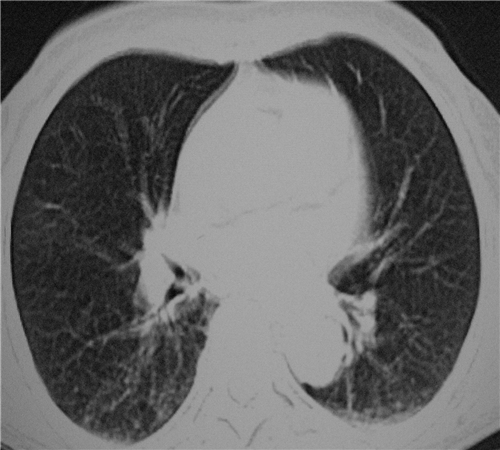

标题: CT26849:女67岁反复胸痛两天余,临床考虑夹层。 [打印本页]

标题: CT26849:女67岁反复胸痛两天余,临床考虑夹层。

右肺感染,未见夹层。

1)右肺感染性病变。2)建议行ct增强扫描或mri检查排除主动脉夹层。

双下肺感染,右侧显著。有无夹层,增强扫描后再诊断。

1.考虑双肺感染,右侧为重;2.建议ct增强或mri排除主动脉夹层

双下肺感染,右侧显著。有无夹层,增强扫描后再诊断。食道未见异常。

平扫未见确切夹层征,建议必要时增强扫描或mri检查。